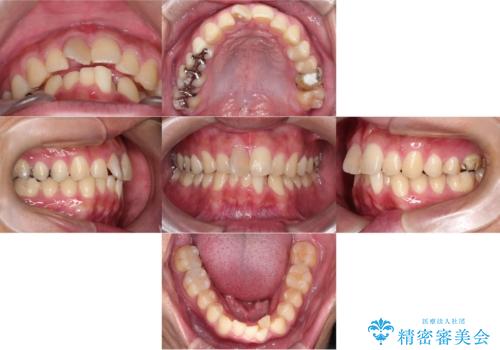

【インビザライン 非抜歯】歯の捻じれと歯のでこぼこを治したい!

- 「上の前歯の捻じれと下の前歯のでこぼこを治したい」を主訴に来院された患者様です。

矯正検査の結果、非抜歯で矯正可能だったためインビザラインで治療を行いました。

アーチの拡大とIPRで叢生を改善いました。

11ヵ月で矯正を終える事ができ患者様も大変ご満足されていました。